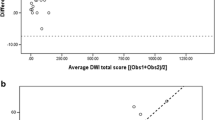

MRI sensitivity for detecting severe CF bronchiectasis was 0.33 (CI 0.09-0.57), while specificity was 100 % (CI 0.88-1). ICCs for bronchiectasis and trapped air were as follows: MRI-bronchiectasis (0.79); CT-bronchiectasis (0.85); MRI-trapped air (0.51); CT-trapped air (0.87). Bland-Altman plots showed an MRI tendency to overestimate the severity of bronchiectasis in mild CF disease and underestimate bronchiectasis in severe disease.

Inter- and intra-observer agreement, expressed as ICCs, for MRIobs1 vs. MRIobs2, CTobs1 vs. CTobs2, MRImean obs 1+2 vs. CTmean obs 1+2, CTobs1 vs. CTobs1 and MRIobs1 vs. MRIobs1 are summarised in Table 3. In summary, the inter- and intra-observer agreement for MRI was good or very good, although lower than for CT. The ICCs for CF-CT sub-scores were higher compared to CF-MRI sub-scores, especially for peribronchial thickening and trapped air. Trapped air measurement by MRI did not match with CT as showed by the ICC values: CT-trapped air (0.87); MRI-trapped air (0.51) and MRI/CT-trapped air (0.46). Finally, the intra-observer agreement for the observer 1, who repeated the score twice, was overall very good, but lower for MRI than for CT. Bland-Altman and identity plots showed that PROPELLER MRI, for almost all sub-scores, tends to overestimate mild CF cases and underestimate severe CF cases (Figs. 1 and 2).

Bland-Altman plot of MRImean obs 1+2 vs. CTmean obs 1+2. All scoring data are numerical and scores are expressed as percentage of the maximal possible score. Horizontal axis: average bronchiectasis sub-score [(MRImean + CTmean)/2]; vertical axis = difference in the bronchiectasis sub-score (MRImean - CTmean). Red and green lines represent mean and ±2 standard deviations (SD) respectively